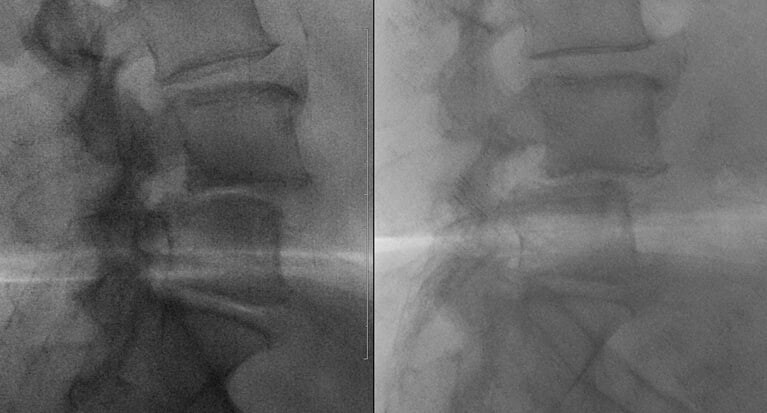

Пациент делает рентгеновские снимки не просто стоя, а в максимальном наклоне вперед и назад. Это показывает, как ведут себя позвонки в движении. Смещение, которое было незаметно в статике (на МРТ или КТ), может явно проявиться при сгибании-разгибании.

Бывает, что спондилолистез, четко видимый на МРТ, оказывается стабильным на функциональных снимках — то есть позвонки не «ездят» друг относительно друга при движении. И наоборот, вроде бы небольшая проблема на МРТ может маскировать серьезную нестабильность.